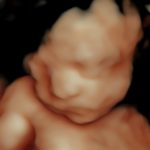

4D/5D/HD Ultrasound Gallery

Gallery